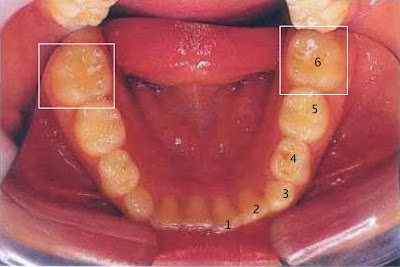

Perhatikan gambar berikut ini….

| Gambar 2. Gigi anak pada peiode gigi bercampur. Gigi susu : gigi nomor 1-5, Gigi geraham tetap pertama : nomor 6 |

Gigi geraham pertama tumbuh di belakang gigi geraham susu paling belakang, sekitar usia 6-8 tahun. Gigi geraham, dengan permukaannya yg berceruk adalah gigi & bagian permukaan gigi yang paling sering terkena karies. Geraham pertama tetap ini semakin rentan terkena karies karena tumbuh pada saat gerakan motorik anak menyikat gigi masih kurang optimal. Kadang anak-anak menyikat gigi cepat-cepat, tidak mencapai bagian paling belakang gigi dsbnya. Sehingga seringkali kami menemukan gigi geraham tetap ini sudah terlanjut berlubang pada anak-anak.